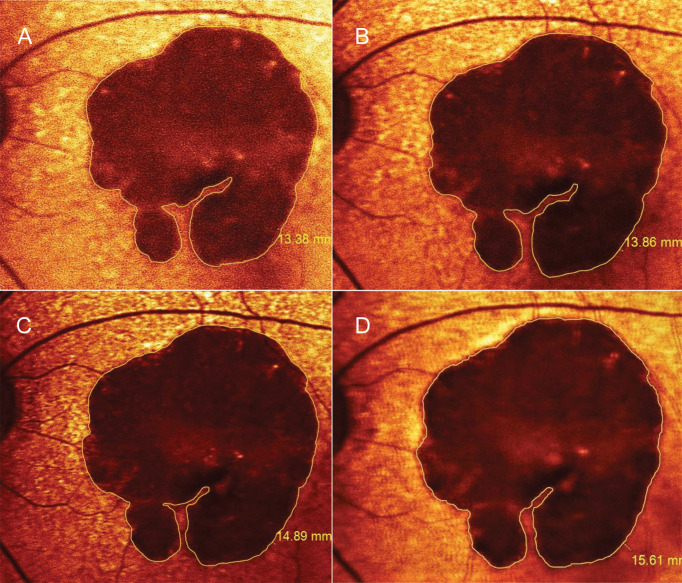

Material and methods: In this retrospective cohort study, patients with unifocal GA were consecutively enrolled (one eye per patient) from 2018 to 2021. The patients were categorized as 1. those receiving dual antiplatelet therapy containing a daily dose of 75 mg clopidogrel plus 81 mg aspirin (DAPT group), and 2. those not receiving DAPT (control group). Areas of GA, based on red-filtered fundus autofluorescence, were measured at baseline, and at 3, 6, and 12 months. The primary outcome was absolute 12-month changes in the square root (SQRT) area.

Results: One eye in each group developed neovascular AMD and was excluded from the analysis. The DAPT (24 eyes) and control (22 eyes) groups had comparable age and baseline SQRT area (1.2 ± 0.27 and 1.8 ± 0.41 mm, respectively; p adjusted for age = 0.23). At 12 months, after controlling for age and the presence of soft drusen or reticular pseudodrusen, patients receiving DAPT had fewer changes in the SQRT area than that of the control group (0.097 vs. 0.17 mm; p = 0.02). The presence of drusen significantly predicted increased GA growth and choroidal thickness reduction.